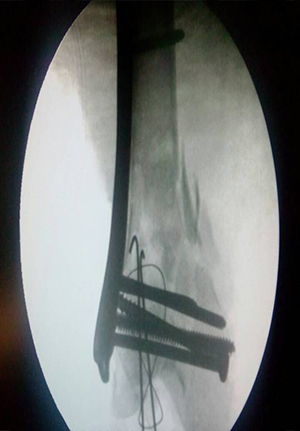

Proximal femoral nail for comminuated subtrochanteric fracture